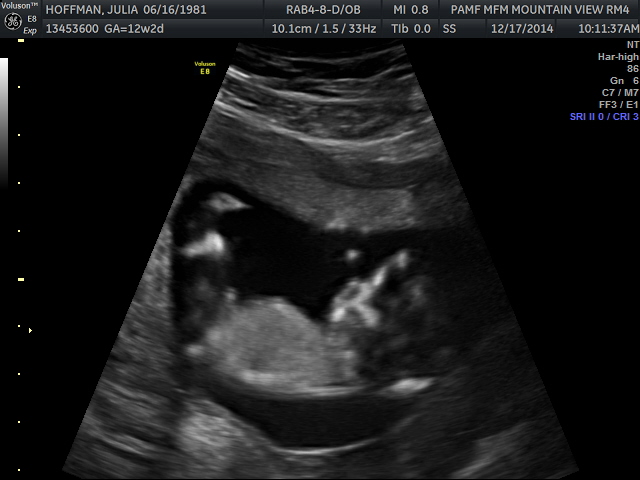

Posting for a friend. Ultrasound tech had 70% girl guess. Would love to know your thoughts!

I actually think boy, it looks like the nub is rising.